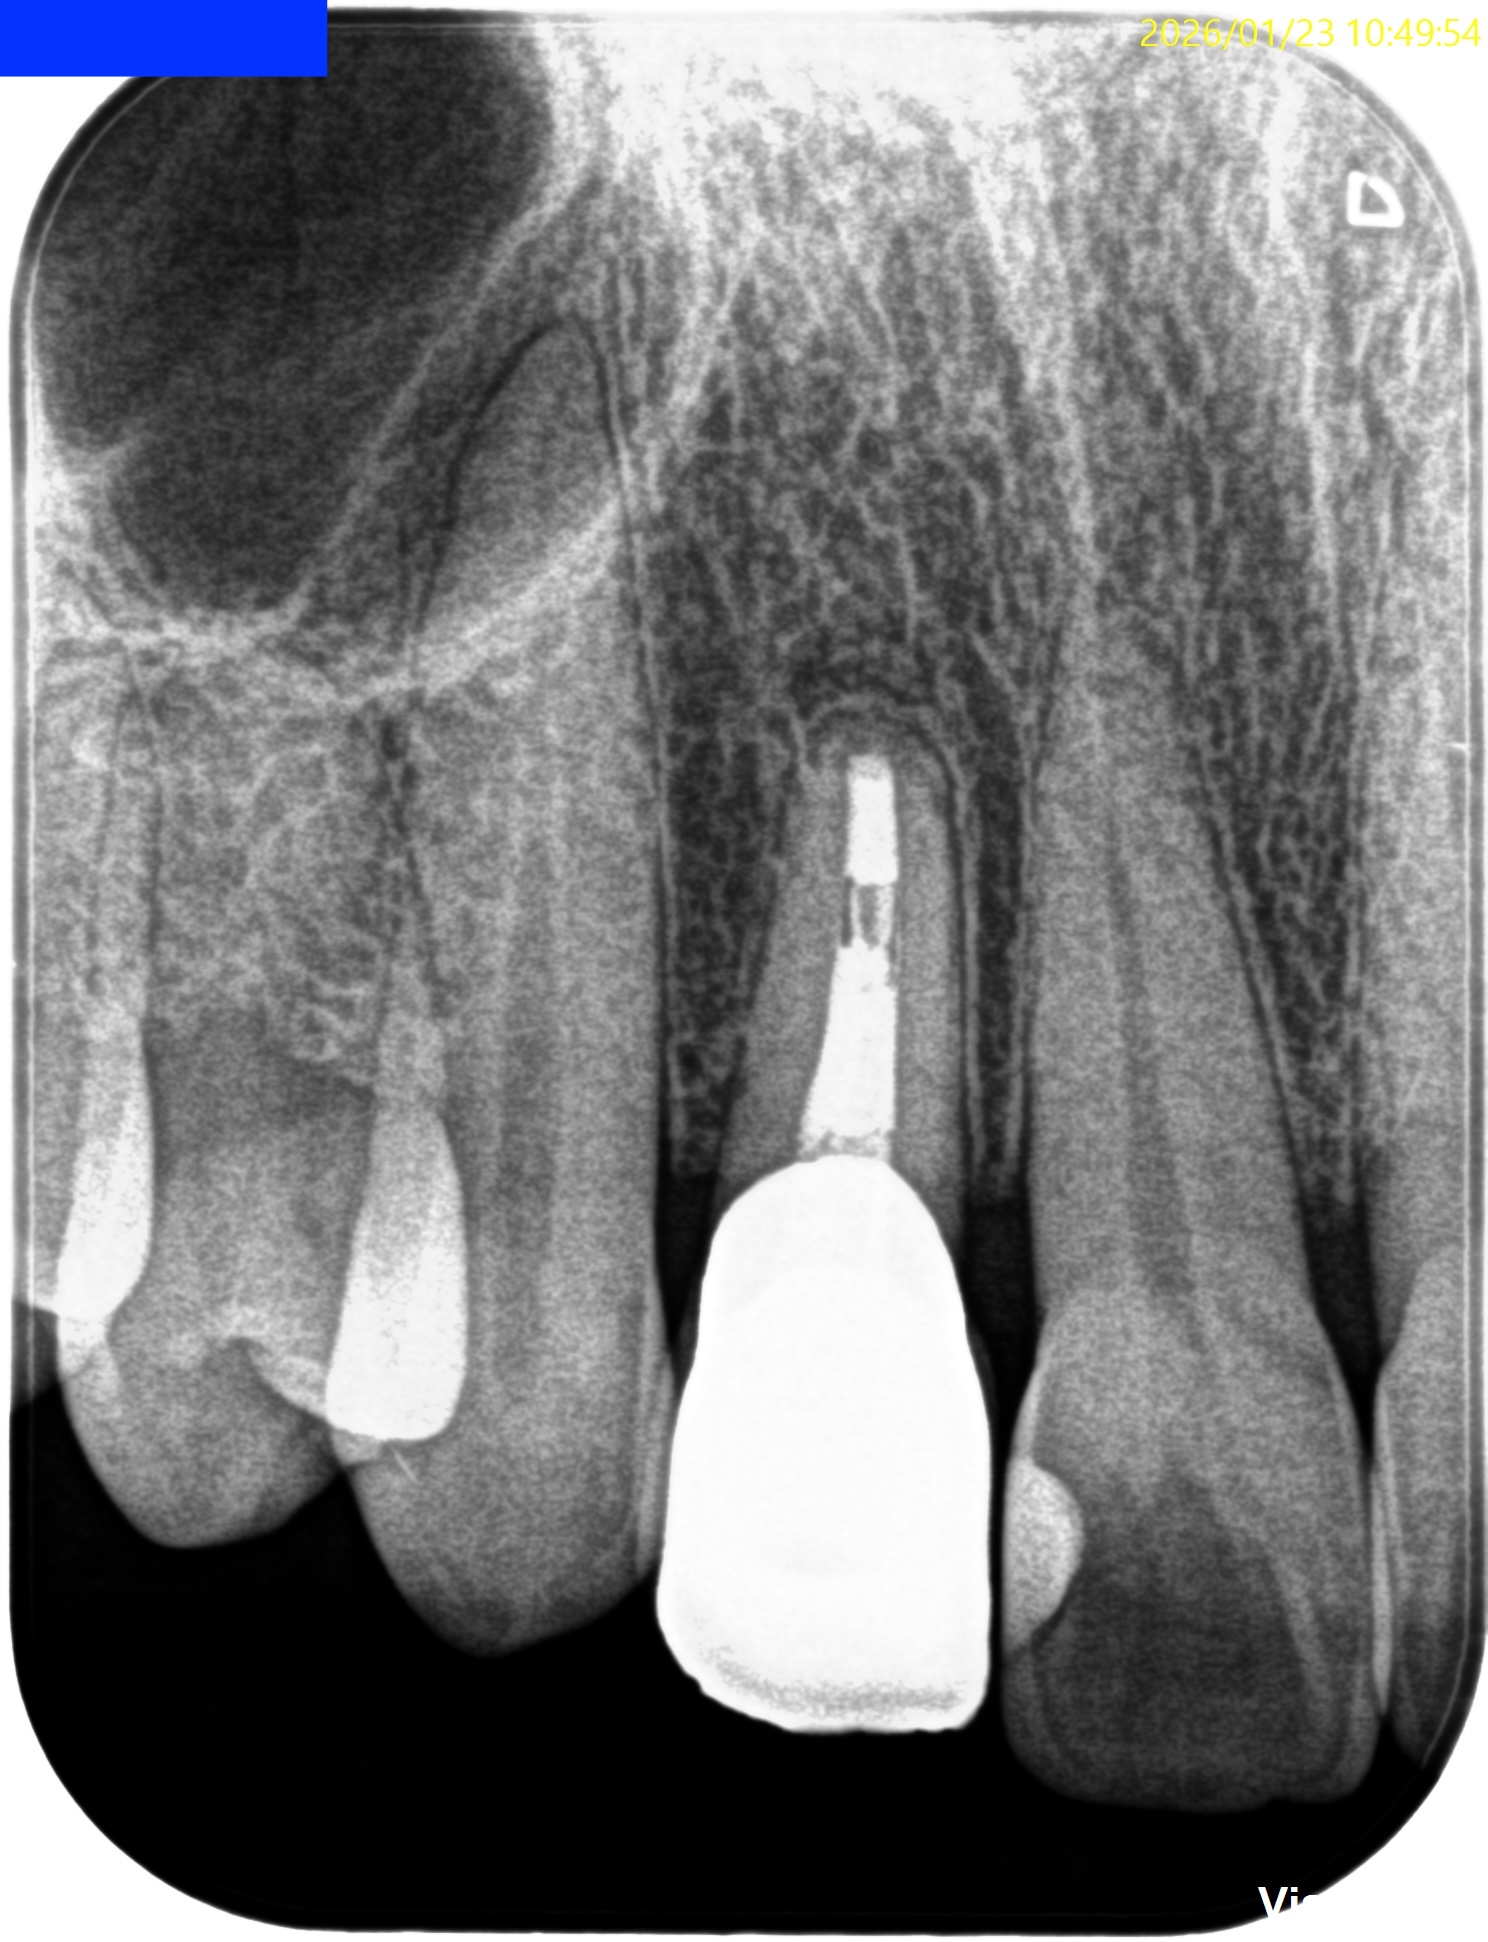

根尖が既に開いており、圧痛があったことから治療は再根管治療ではなく、歯根端切除術であるということがわかる。

その際は、

クラウンのマージンより11.5mm下方に#7のApexはあり、そこを3mm切断するには頬舌的に4.4mmの幅があるということがわかる。

術後にPA, CBCTを撮影した。

気泡が逆根管充填材に混入したが、問題はないだろう。

初診時と比較した。

気泡は入ったが劇的に治癒し、臨床症状もないことからこの日で終診となった。